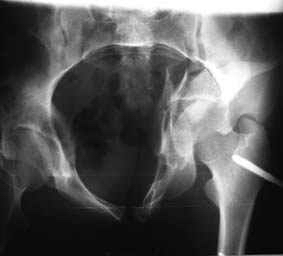

Все-таки надо бы начать не с КТ, а с обзорного снимка таза и косых проекций впадины.

Это обзорные и косые снимки